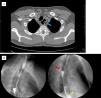

Durante el ingreso se estudia mediante una TC de tórax y un tránsito esofagogástrico (figs. 1A y B) donde se evidencia una doble luz esofágica, sospechando una duplicación esofágica congénita. Se realiza una fibrogastroscopia que muestra un ostium a 24cm de arcada dentaria que corresponde al orificio que conecta la segunda luz esofágica (fig. 2A). Se toman biopsias de la mucosa con aspecto inflamatorio sin evidencia de malignidad en el análisis anatomopatológico. El diagnóstico explica los cuadros de neumonías recurrentes desde la infancia y la disfagia por impactación del ingreso.

A) TC corte axial: El esófago cervical se muestra dilatado con una doble luz en su interior, sin comunicación con la tráquea (flecha azul). B) Tránsito esofagogástrico. Se observa el contraste oral discurriendo a través del esófago hasta a unión esofagogástrica (asterisco amarillo) y hacia la segunda luz esofágica, donde permanece estásico (flecha roja).